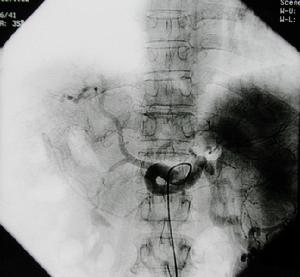

脾動脈栓塞術治療治療原則